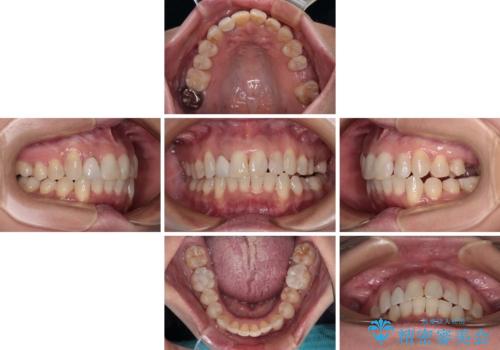

前歯のデコボコとむし歯治療の跡 インビザライン矯正とオールセラミッククラウン治療

- 前歯のセラミッククラウンの縁が見えることが気になってから、デコボコも気になるようになってきたとのことで来院された患者様です。

デコボコの程度は中等度であったため、インビザライン・モデレートパッケージにて歯列を整えることとしました。

セラミッククラウンの装着されていた前歯と、大きな修復治療の跡がある反対側の歯は、矯正治療後に補綴治療を行うこととしました。